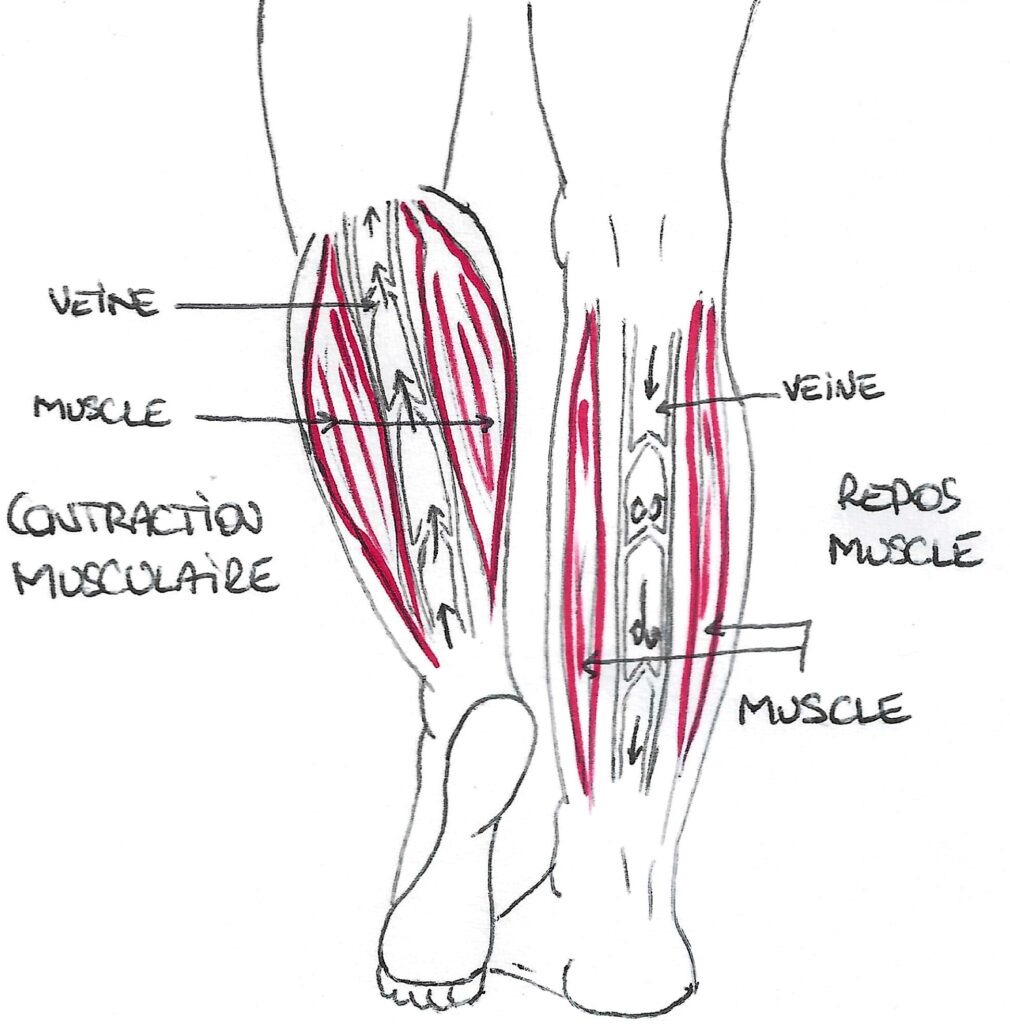

- les mouvements de pompes musculaires : les muscles de la jambe et de la cuisse entourent les tuyaux et lors de leurs contraction, ils appuient sur le tuyau, faisant avancer le liquide.